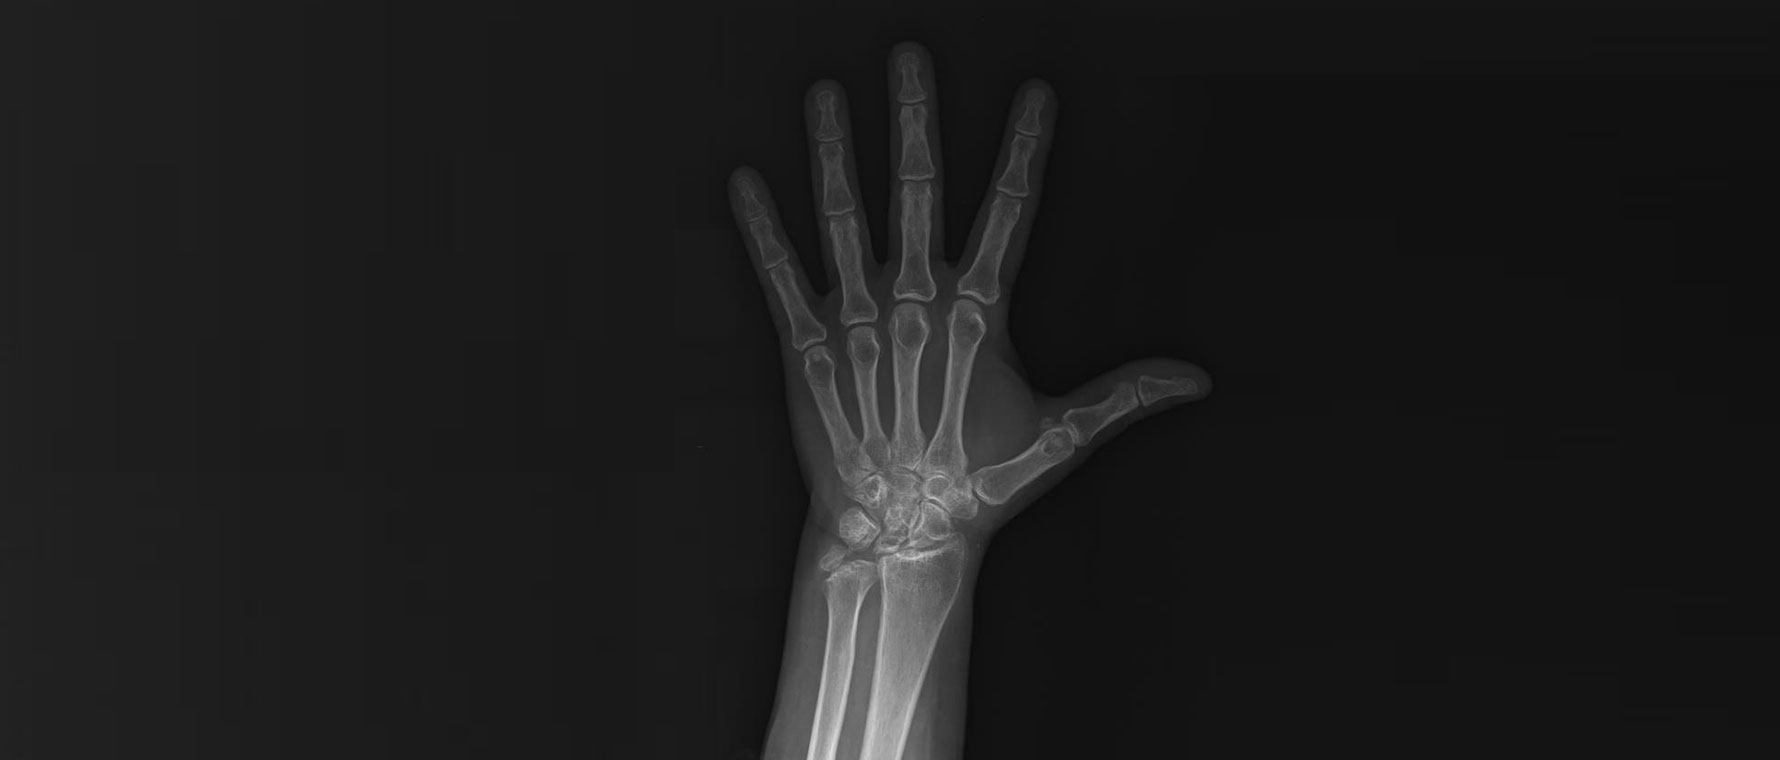

Parmak eklemlerinde kireçlenme, eklem kıkırdağının zamanla aşınması sonucu ortaya çıkan bir durumdur. Genellikle yaşla birlikte gelişir, ancak geçirilmiş travmalar ve yoğun kullanım da etkili olabilir. Hastalarda ağrı, şişlik, sertlik ve parmaklarda şekil değişikliği görülebilir. Sabah tutukluğu sık bir şikâyettir. Tanı muayene ve röntgen ile konur. Tedavide ağrı kesici ilaçlar, egzersizler, atel kullanımı ve eklem içi enjeksiyonlar uygulanabilir. Şikâyetleri ileri düzeyde olan hastalarda cerrahi seçenekler gündeme gelir.

Başparmak Kök Eklem Kireçlenmesi (1.cmc Eklem Artrozu)

Başparmak kök eklem kireçlenmesi, başparmağın bileğe bağlandığı eklemde kıkırdağın aşınmasıyla ortaya çıkar. Özellikle kavrama ve sıkma hareketlerinde ağrıya yol açar. Hastalar kapak açma, anahtar çevirme gibi işlerde zorlanır. Zamanla şekil bozukluğu gelişebilir. Tanı muayene ve röntgen ile konur. Tedavide atel, ilaçlar, egzersiz ve enjeksiyonlar uygulanır. Şikâyetleri ileri düzeyde olan hastalarda cerrahi seçenekler gündeme gelir. Cerrahi artroskopik ya da açık cerrahilerle kireçlenen kemik yüzlerinin tıraşlanması ve başparmak kök eklemini yerinde tutan bağların çevre tendonlarla onarılmasını içerir.